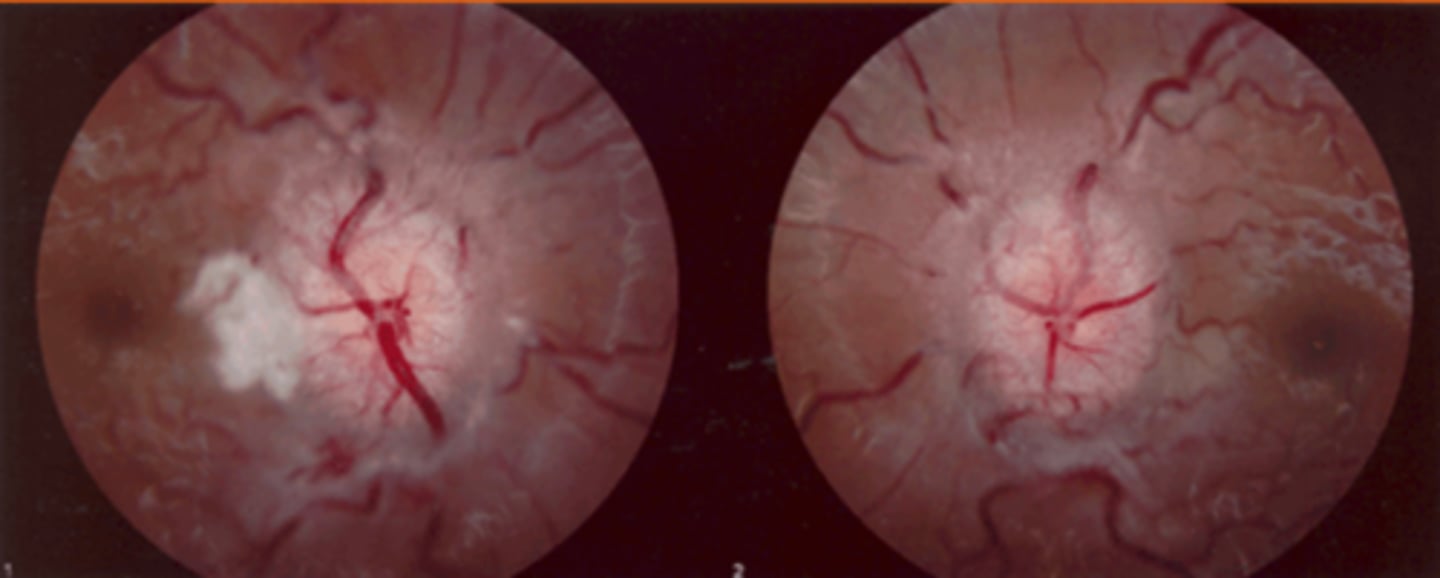

What cause of ascending optic atrophy is shown here?

RP